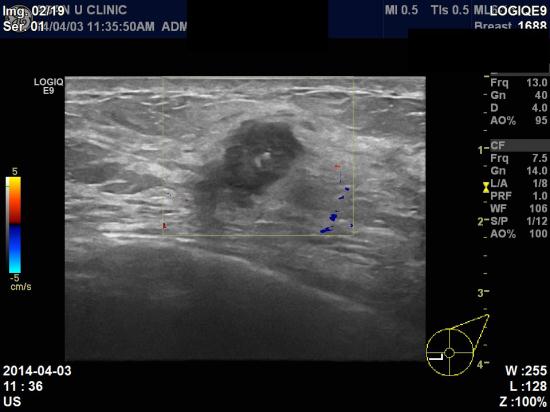

본원 초음파 검사상

우측유방 8시 방향 젖꼭지에서 5cm 떨어진 부위에 0.85 cm 의 종괴가 발견되었고,

유방중심핵생검(조직검사)결과 침윤성 유관암으로 진단되었습니다.